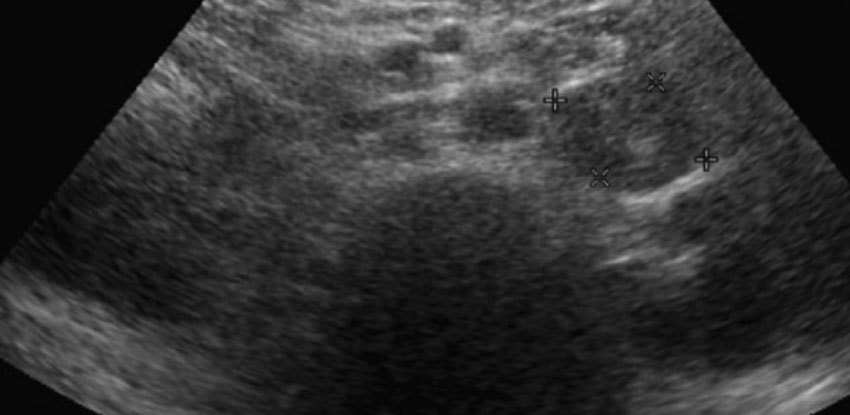

Согласно данным современных научных исследований, ни один метод диагностики метастазов рака в надпочечниках не обладает 100% точностью и не может считаться золотым стандартом. Наиболее информативны: компьютерная томография, МРТ и ПЭТ-КТ.

КТ и МРТ позволяют ориентировочно судить о злокачественной природе новообразования по содержанию в нем липидов (жиров). Для доброкачественных опухолей надпочечников характерно высокое содержание липидов, а для злокачественных — низкое. Но это не абсолютно надежный критерий.

Основные признаки злокачественных опухолей надпочечников во время КТ:

Относительно высокая плотность.

При введении пациенту контрастного раствора, он задерживается в опухоли.

Образование более 4 см в диаметре с более высокой вероятностью окажется злокачественной опухолью.

Рост по результатам контрольного исследования через 6 месяцев.

Признаки прорастания в соседние ткани.

Неровные, нечеткие границы.

Центральный некроз — участок гибели ткани внутри опухоли.

КТ и МРТ лучше всего подходят для диагностики доброкачественных новообразований надпочечников и исключения злокачественного процесса.